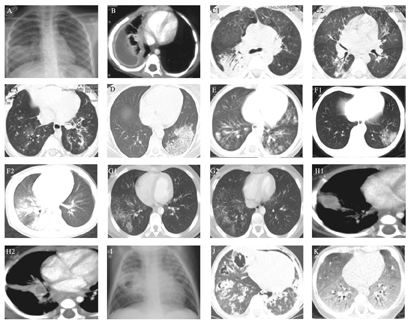

肺炎链球菌(图2A)典型表现为大叶性肺炎。少数患者可表现为支气管肺炎、球形肺炎。

A.链球菌感染大叶性肺炎;B.金黄色葡萄球菌感染右下肺脓肿形成;C1、C2、C3.腺病毒肺炎;D.流感病毒肺炎;E.呼吸道合胞病毒肺炎;F1、F2.新型冠状病毒肺炎;G1、G2.支原体肺炎;H1、H2.结核杆菌感染原发综合征;I.结核性空洞;J.曲霉菌肺炎;K.卡氏肺孢子虫肺炎。

金黄色葡萄球菌(图2B)毒力强且容易液化坏死,其感染具有一定的特征性。进展迅速,一日内甚至几小时内由肺小叶进展至肺段或肺叶,由单侧进展至双侧。并以伴发肺大泡和胸膜炎为特征。由于支气管内有炎性渗出物堵塞,所以实变区无支气管充气征,CT上可见小叶中心结节和树芽征,表现为支气管肺炎,融合时形成弥漫性实变。多有含气液平的空洞性结节(直径4~10 mm)。病变数小时到两天内出现肺大泡,内无气液平,血源性感染者好发于两肺胸膜下及基底部,肺大泡出现少量液体时提示继发新感染。肺大泡多发者类似蜂窝肺[17]。该菌易累及胸膜,引起胸膜炎、胸腔积液或脓胸,且易分房或包裹。因此肺炎早期即出现肺大泡、胸腔积液或积脓、脓气胸时多提示金黄色葡萄球菌感染。

腺病毒感染(图2 C1、C2、C3)常见于婴幼儿或免疫功能低下者,儿童腺病毒感染以肺气肿和双肺多发磨玻璃影、实变影为主要特征[19],且实变多呈向心性分布。早期支气管黏膜水肿增厚、坏死,导致换气功能障碍,影像学表现为间质病变,肺气肿。病情进展,3~7 d出现两肺多发片状实变影,CT影像学表现为小叶中心性结节和树芽征为特点的支气管肺炎,病灶迅速融合,形成大片实变、弥漫性肺部浸润影,实变周围肺组织呈现肺气肿,支气管及其周围形成间质性肺炎表现。腺病毒肺炎后遗症期主要以闭塞性毛细支气管炎、间质纤维化、支气管扩张、单侧透明肺为特征的Swyer-James-McLeod综合征。闭塞性毛细支气管炎X线上最主要特征为肺气肿,CT上的特征性表现为马赛克灌注[19]。

流感病毒感染(图2D)常见影像学表现为磨玻璃影,网格状结节影[20],常位于肺下叶,部分合并实变,容易出现继发性感染。病灶迅速融合时,可形成大叶性实变[21],除病变导致严重的肺泡损伤外,常为合并肺炎链球菌、金黄色葡萄球菌等细菌性感染。

呼吸道合胞病毒感染(图2E)常表现为肺气肿和肺不张、间质性肺炎[22],可有两肺斑片状渗出影(支气管肺炎),CT上表现为小叶中心性结节和树芽征。

新型冠状病毒肺炎X线胸片表现为两肺中外带和胸膜下的局限性斑片状或多发节段性片状渗出影,重型为多发实变,危重型呈"白肺"表现。CT表现为两肺多发斑片状磨玻璃影、实变影,以沿支气管血管束和胸膜下分布为主,可见细网格状影,呈铺路石征。病变进展期表现为磨玻璃影、实变、结节等多种性质病变共存,以肺中外带和胸膜下、肺底分布为主,可有纤维化表现[23]。马慧静等[24]报道儿童病例CT影像学表现(图2 F1、F2)与成人患者典型表现相同。

X线表现早于重于肺部体征。早期表现为间质性肺炎,最常见影像学表现为一侧或双侧下肺野的斑片状影或模糊的网状结节影,多呈支气管肺炎表现,少数患儿可伴有胸腔积液。CT见小叶性分布的磨玻璃影和实变影,可有中央小叶结节影和树芽征[25]。

儿童最常见的异常是淋巴结肿大,可见于90%~95%的患儿,最常累及右支气管旁和肺门淋巴结。原发性肺结核典型表现为原发病灶、淋巴管炎、肺门淋巴结肿大形成哑铃形的原发综合征。绝大部分儿童患者有淋巴结肿大和肺实变。少数患儿有胸腔积液[26]。继发性血源性肺结核多形成粟粒性结节影。典型X线表现为从肺尖到肺底弥漫性大小均匀、密度均匀、分布均匀的圆形或椭圆形直径1~2 mm边界清楚的粟粒状结节影。CT除粟粒样表现,还可有磨玻璃影、淋巴结肿大等表现。干酪性肺炎可有多个不规则的虫蚀样空洞[27]。结核患者中,CT上树芽征被认为是活动性肺结核的可靠标志[28]。